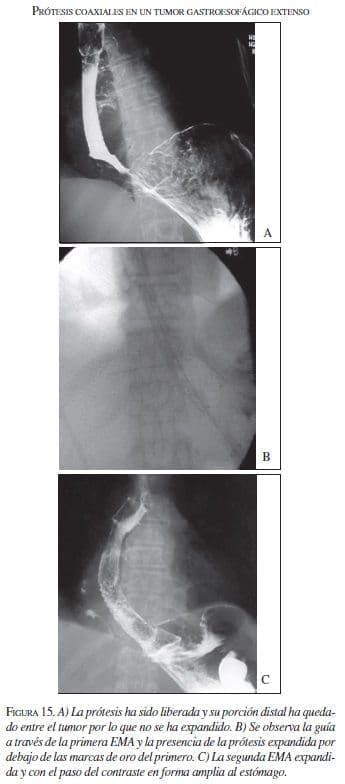

Además de las tres EMA que se colocaron por migración de las primeras, se pusieron dos coaxiales (una prótesis dentro de otra prótesis) cuando el tumor inicial era muy largo y se necesitaba de otro para franquear la totalidad de la extensión del tumor (figura 15).